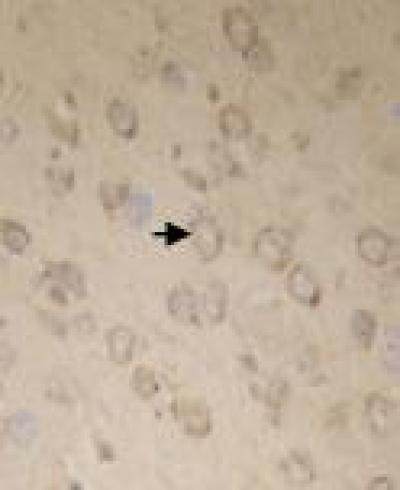

In recent years, neurotoxicity from exposure to low levels of lead in the environment has become increasingly prevalent. Therefore, the discovery of herbs that have lead-eliminating properties without harmful side effects is essential for the management of lead poisoning. Preliminary studies by Yu Wang and colleagues from Longnan Teachers College have verified that olive leaf extract can protect the blood, spleen and hippocampus in lead-poisoned mice. However, little is known about the effects of olive leaf extract on lead-induced brain injury. A recent study from Yu Wang and colleagues investigated brain histological structure and antioxidant capacity in lead-poisoned mice as well as apoptotic factors in the cerebral cortex of mice using transmission electron microscopy, spectrophotometry and immunohistochemical staining. The researchers have confirmed that olive leaf extract can inhibit lead-induced brain injury by increasing antioxidant capacity and reducing apoptosis. These findings, published in the Neural Regeneration Research (Vol. 8, No. 22, 2013), initially reveal the action mechanism underlying olive leaf extract treatment for lead poisoning, and provide scientific evidence and theoretical basis for development and utilization of olive leaf in boosting the body antioxidant capacity and discharging foreign bodies.

Article: " Olive leaf extract inhibits lead poisoning-induced brain injury," by Yu Wang, Shengqing Wang, Wenhui Cui, Jiujun He, Zhenfu Wang, Xiaolu Yang (Department of Biology and Chemistry, Longnan Teacher's College, Chengxian 742500, Gansu Province, China)

Wang Y, Wang SQ, Cui WH, He JJ, Wang ZF, Yang XL. Olive leaf extract inhibits lead poisoning-induced brain injury. Neural Regen Res . 2013;8(22):2021-2029.